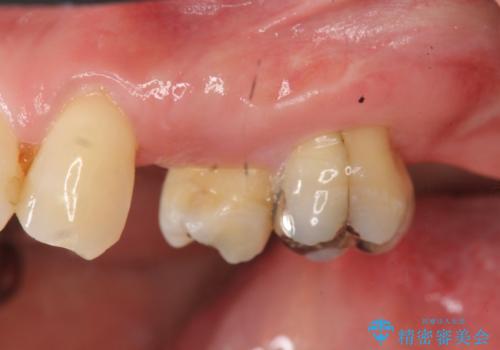

- 左上の歯の喪失し噛みにくいことの改善、歯を入れたいと希望され来院されました。

インプラント治療を行うには隙間が狭すぎるためブリッジか入れ歯をご提案したところ、取り外しの必要な入れ歯は希望されずブリッジを用いて機能・審美性の改善を行っていくこととなりました。

ブリッジの長期的な予後のためには支台となる歯の位置・清掃性が重要となりますが、今回ブリッジを製作するにあたり位置の悪い左上小臼歯を補綴前小矯正を行い位置を改善します。